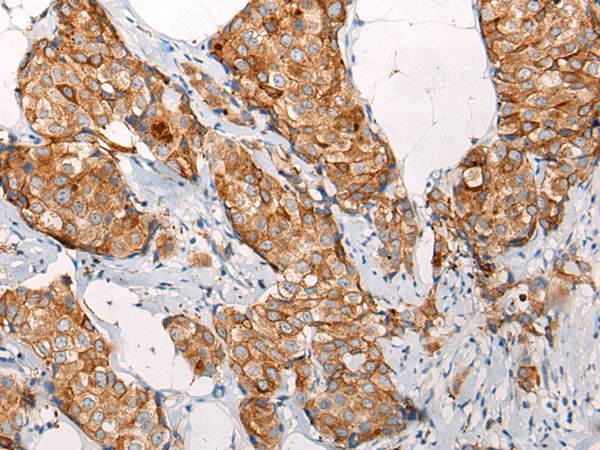

The image on the left is immunohistochemistry of paraffin-embedded Human liver cancer tissue using EMC7 Antibody at dilution 1/35, on the right is treated with synthetic peptide. (Original magnification: x200)

The image on the left is immunohistochemistry of paraffin-embedded Human breast cancer tissue using EMC7 Antibody at dilution 1/35, on the right is treated with synthetic peptide. (Original magnification: x200)